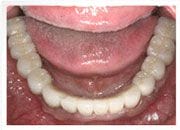

治療後